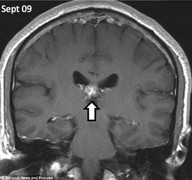

Hình chụp X-quang của một người đàn ông cho thấy anh ta đã bị một con sán dây dài 1cm đào sâu tới 5cm vào não từ trái qua phải.